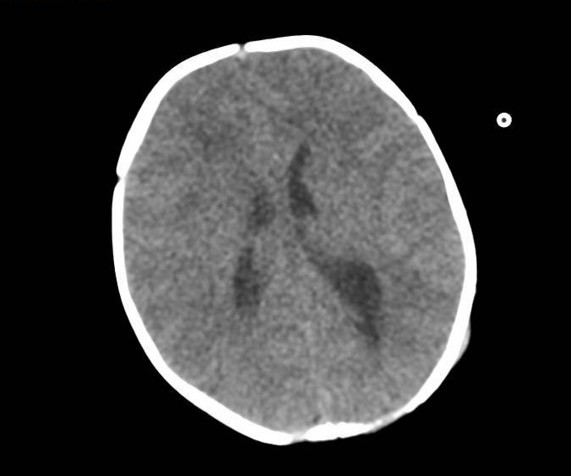

Se realiza tomografía computarizada (TC) craneal urgente al nacimiento (Figura 2).

Figura 2. TC craneal realizada al nacimiento donde no se aprecia hidrocefalia.